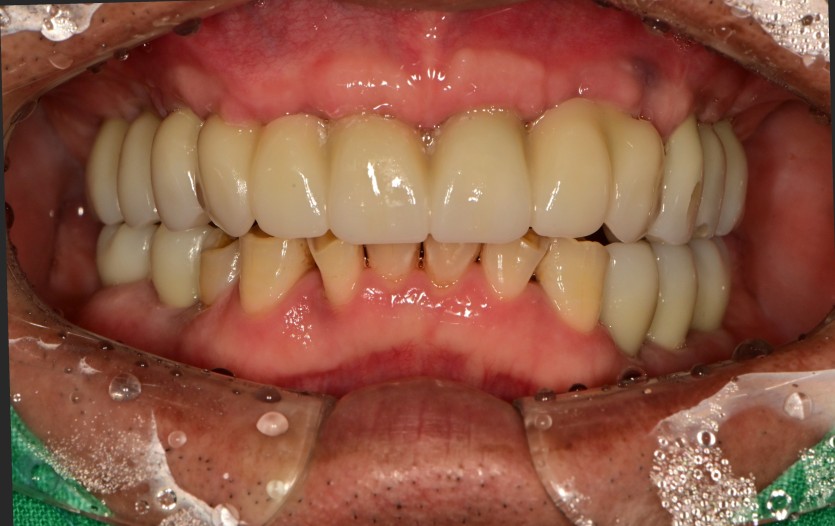

만 60세 상악 전체 임플란트 증례(기존 임플란트 활용)

상악 전체 임플란트 증례입니다.

(타원 임플란트 활용)(하악 일부)

12개의 임플란트로 완성하였습니다.